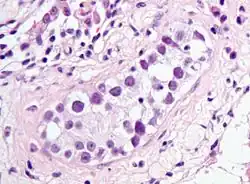

![]() | |

| Intratubular germ cell neoplasia. H&E stain. | |

GCNIS is not palpable, and not visible on macroscopic examination of testicular tissue. Microscopic examination of affected testicular tissue most commonly shows germ cells with enlarged hyperchromatic nuclei with prominent nucleoli and clear cytoplasm. These cells are typically arranged along the basement membrane of the tubule, and mitotic figures are frequently seen. The sertoli cells are pushed toward the lumen by the neoplastic germ cells, and spermatogenesis is almost always absent in the affected tubules. Pagetoid spread of GCNIS into the rete testis is common. Immunostaining with placental alkaline phosphatase (PLAP) highlights GCNIS cell membranes in 95 percent of cases. OCT3/4 is a sensitive and specific nuclear stain of GCNIS.[3]